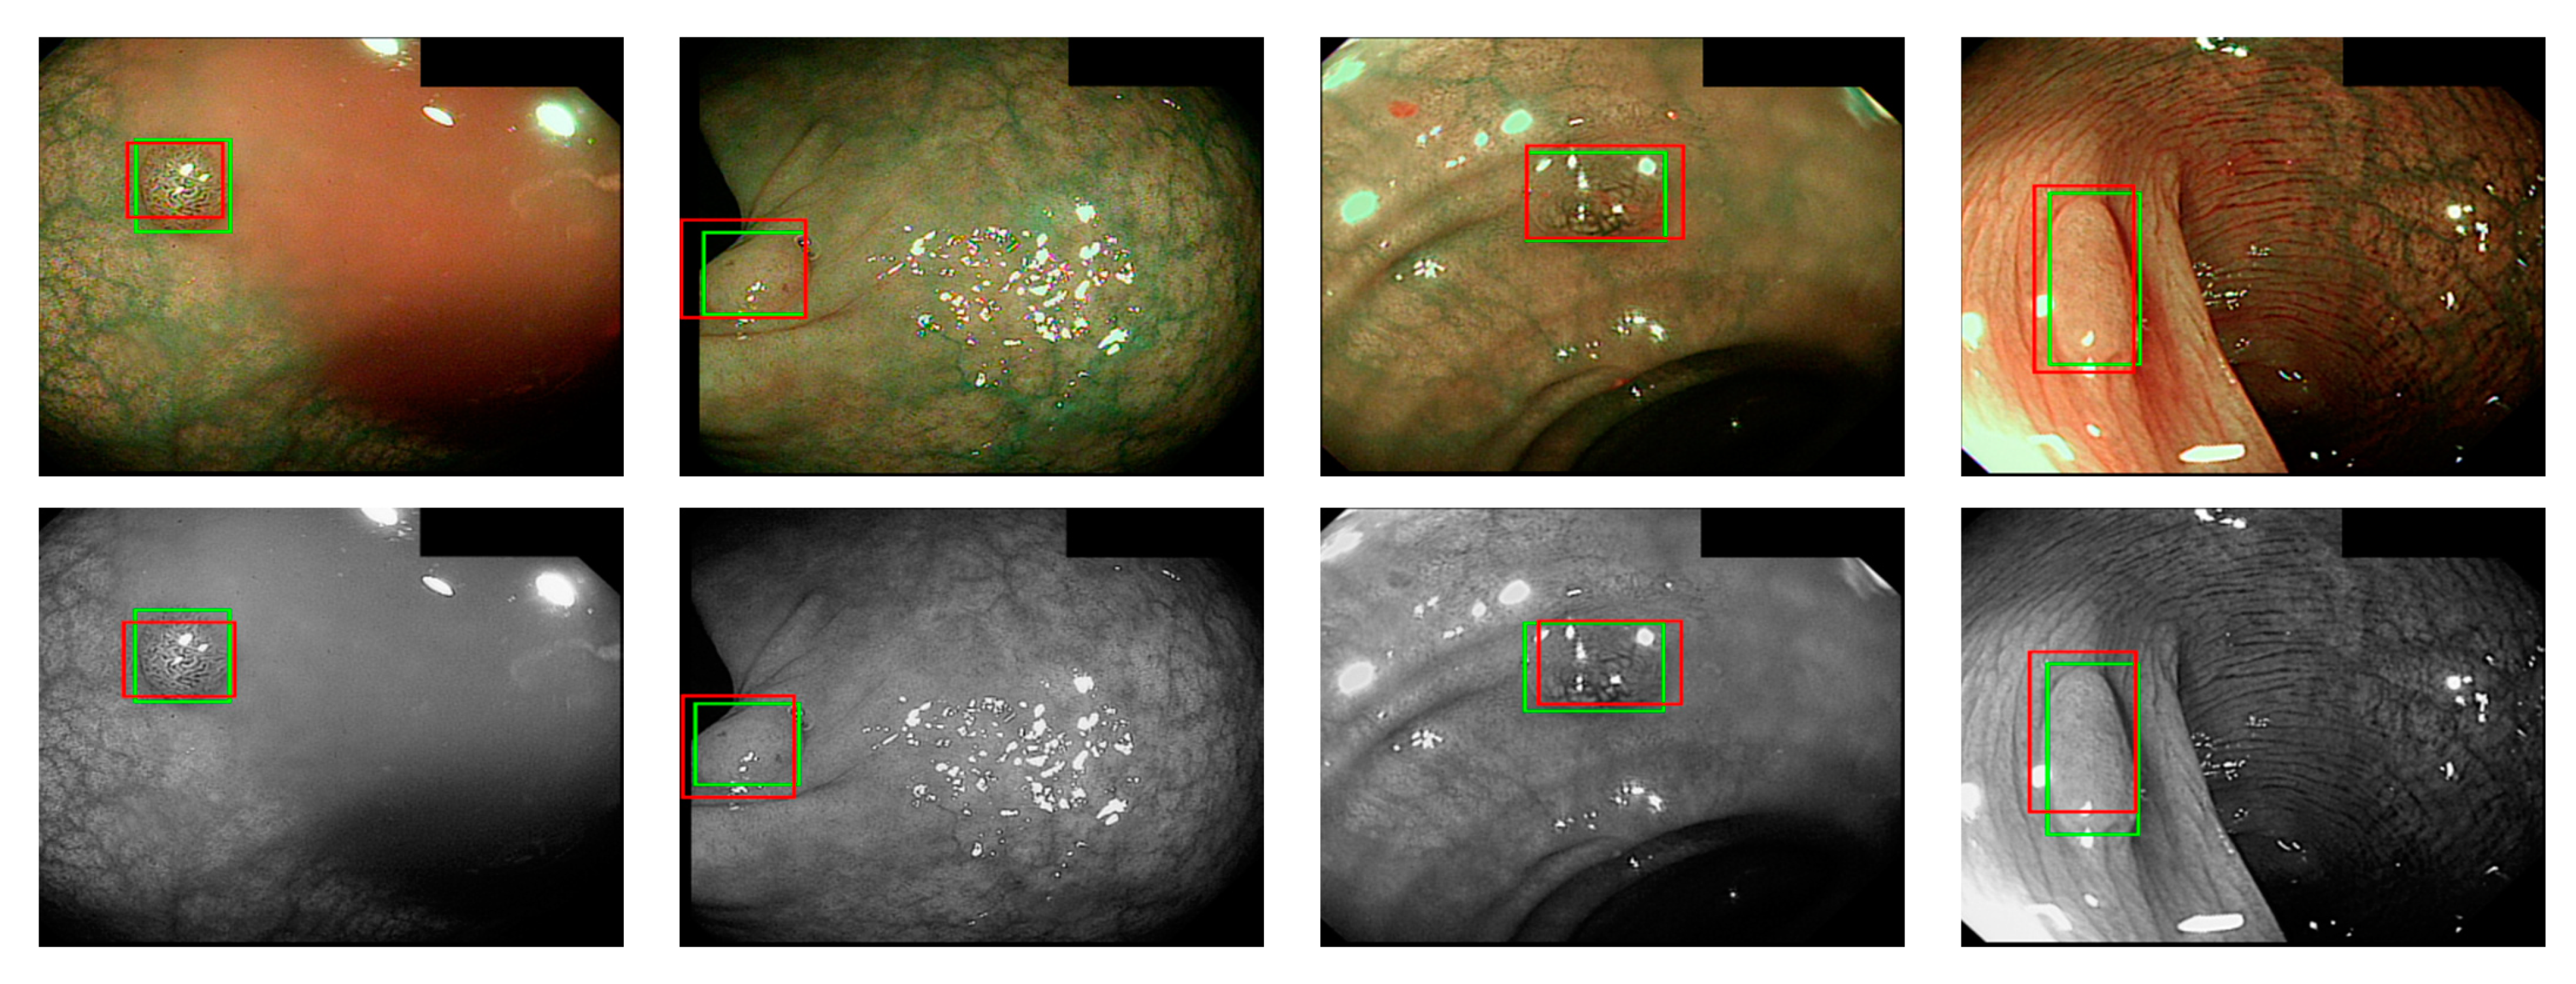

where ai is the input value; p is the pooling regions; n is the pooling size; and aj is the output value after the maximum value is obtained. Polyp detection was then conducted in the bounding box transform layer. The prediction result of the feature map was obtained in the last layer and was output through a 1 × 1 convolutional layer by using a pixel-based approach and converted to a bounding box mode for display [50]. There are eight groups of bounding boxes to locate the polyps: (16, 16), (32, 32), (24, 48), (48, 24), (60, 80), (108, 72), (216, 144), and (180, 180). The cutoff value of polyp detection is 0.2. The size of the predicted bounding box was adjusted by converting it to the range of a true-value bounding box. Table 3 displays the framework of the CNN model. Figure 10 and Figure 11 show the results of WL and NBI polyp detection, respectively, where the first column is the RGB image; the second column is the grayscale image; the red box is the prediction box; and the green box is the actual polyp location marked by the clinician, namely the GT.

Figure 10. WL polyp detection.